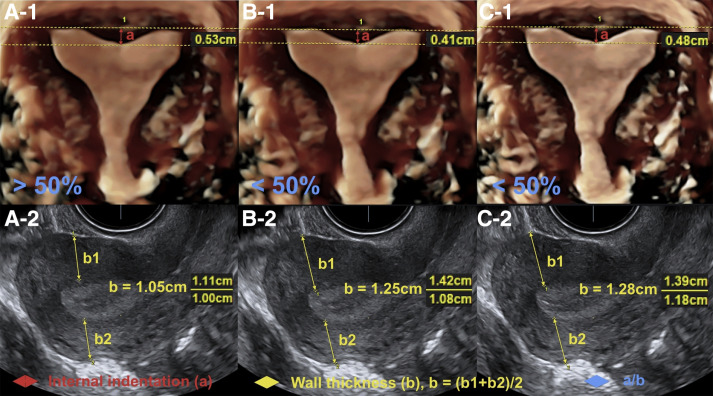

Correct measurements of uterine fundal internal indentation depth and angle: an important but overlooked issue for precise diagnosis of uterine anomalies